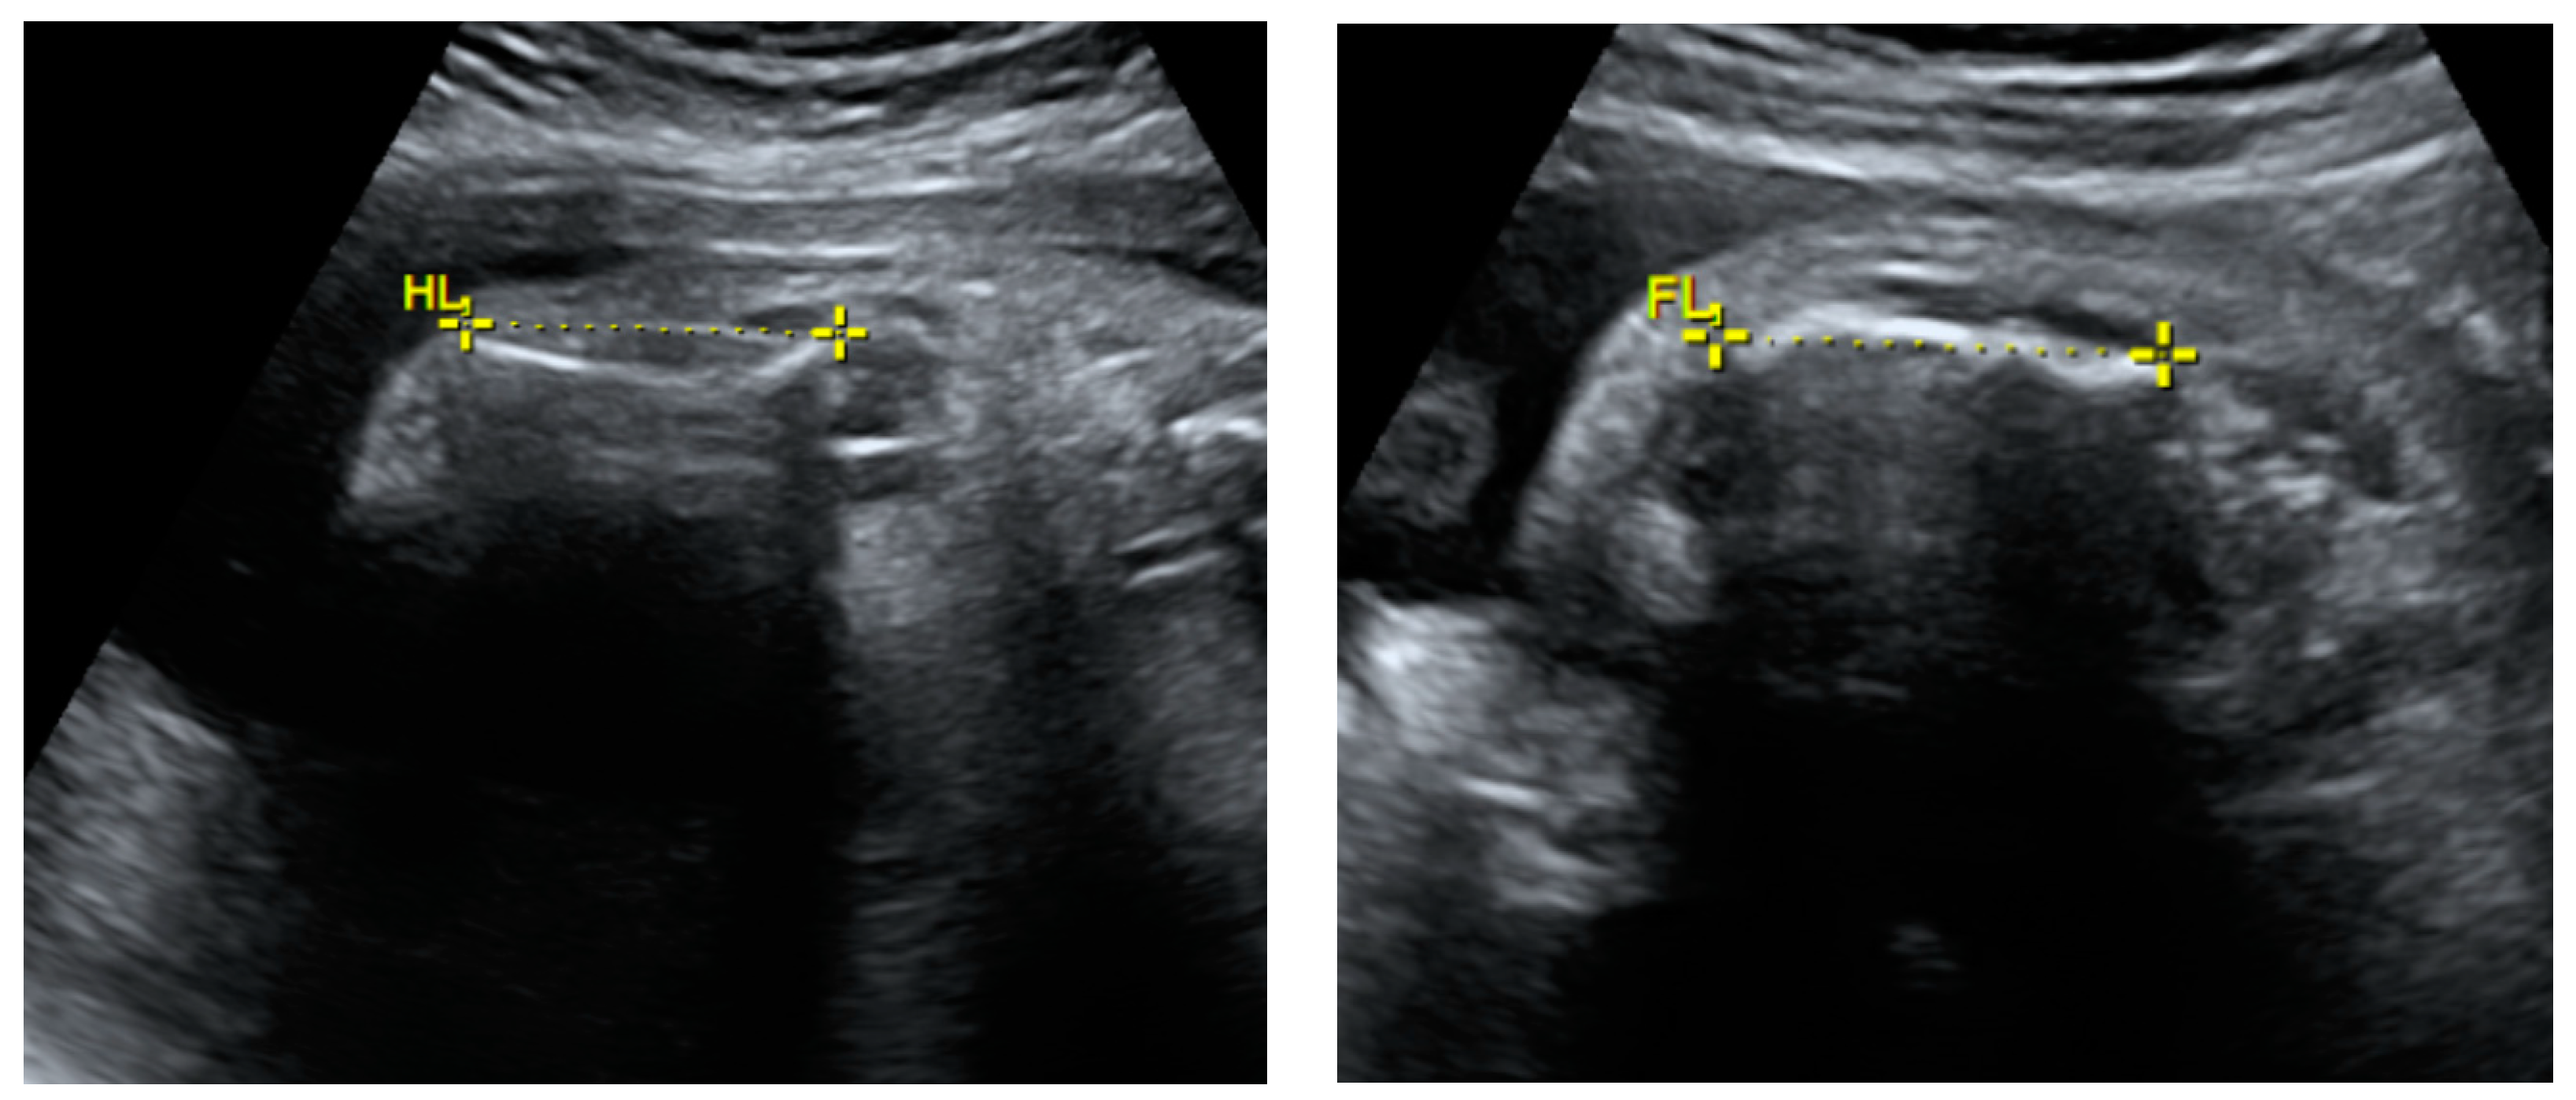

2.1. Prenatal Findings and Further Pregnancy Care